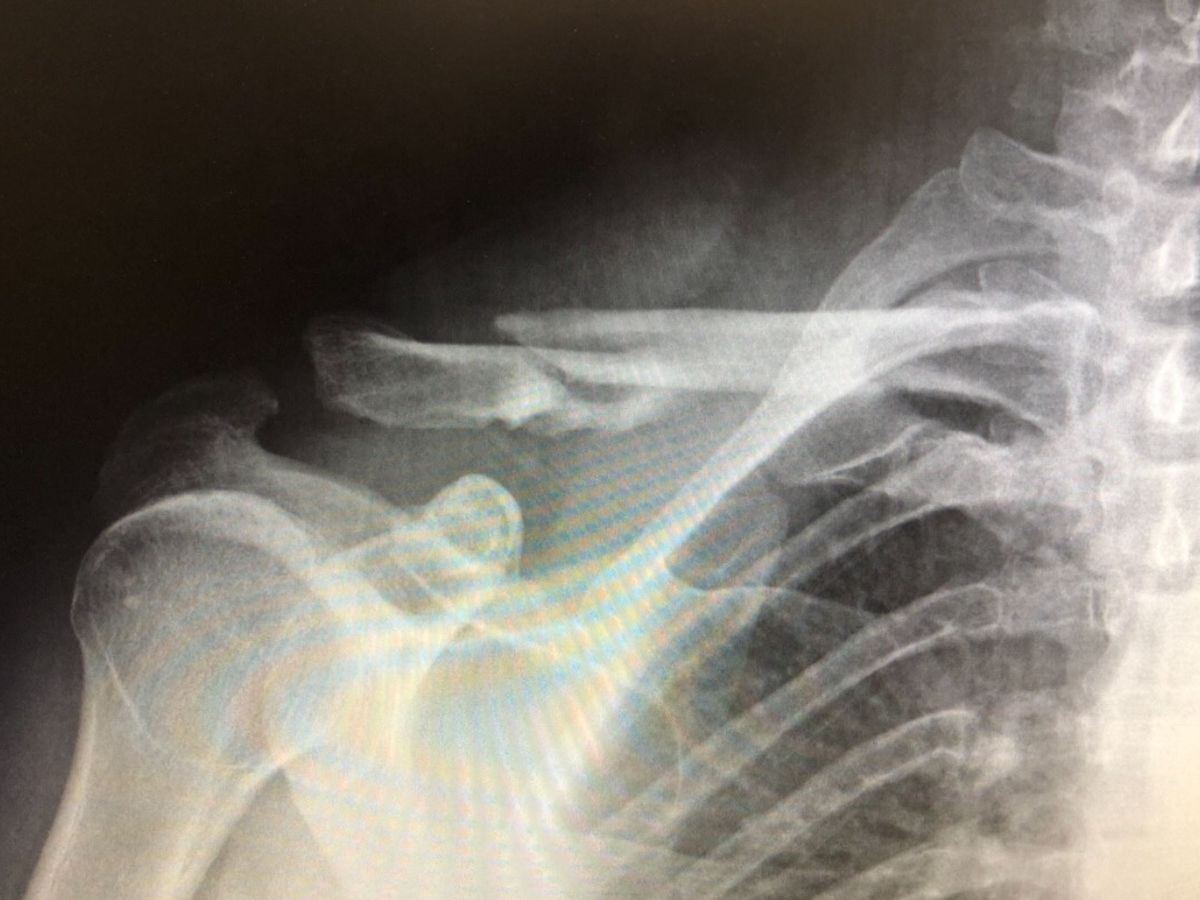

I recently crashed while downhill mountain biking in Colorado. It was at a decent rate of downhill speed causing me to flip over my handlebars absorbing impact onto/into my head/neck/shoulder. This caused a comminuted clavicle fracture that is also displaced with bone fragments all over. My arm is not attached to my body via bone at the moment causing additional pain & stress to the ligaments that typically hold that in place. This particular case will require surgery that is semi invasive to get me to a place that I can function almost fully again to continue with my livelihood, lifestyle & career.